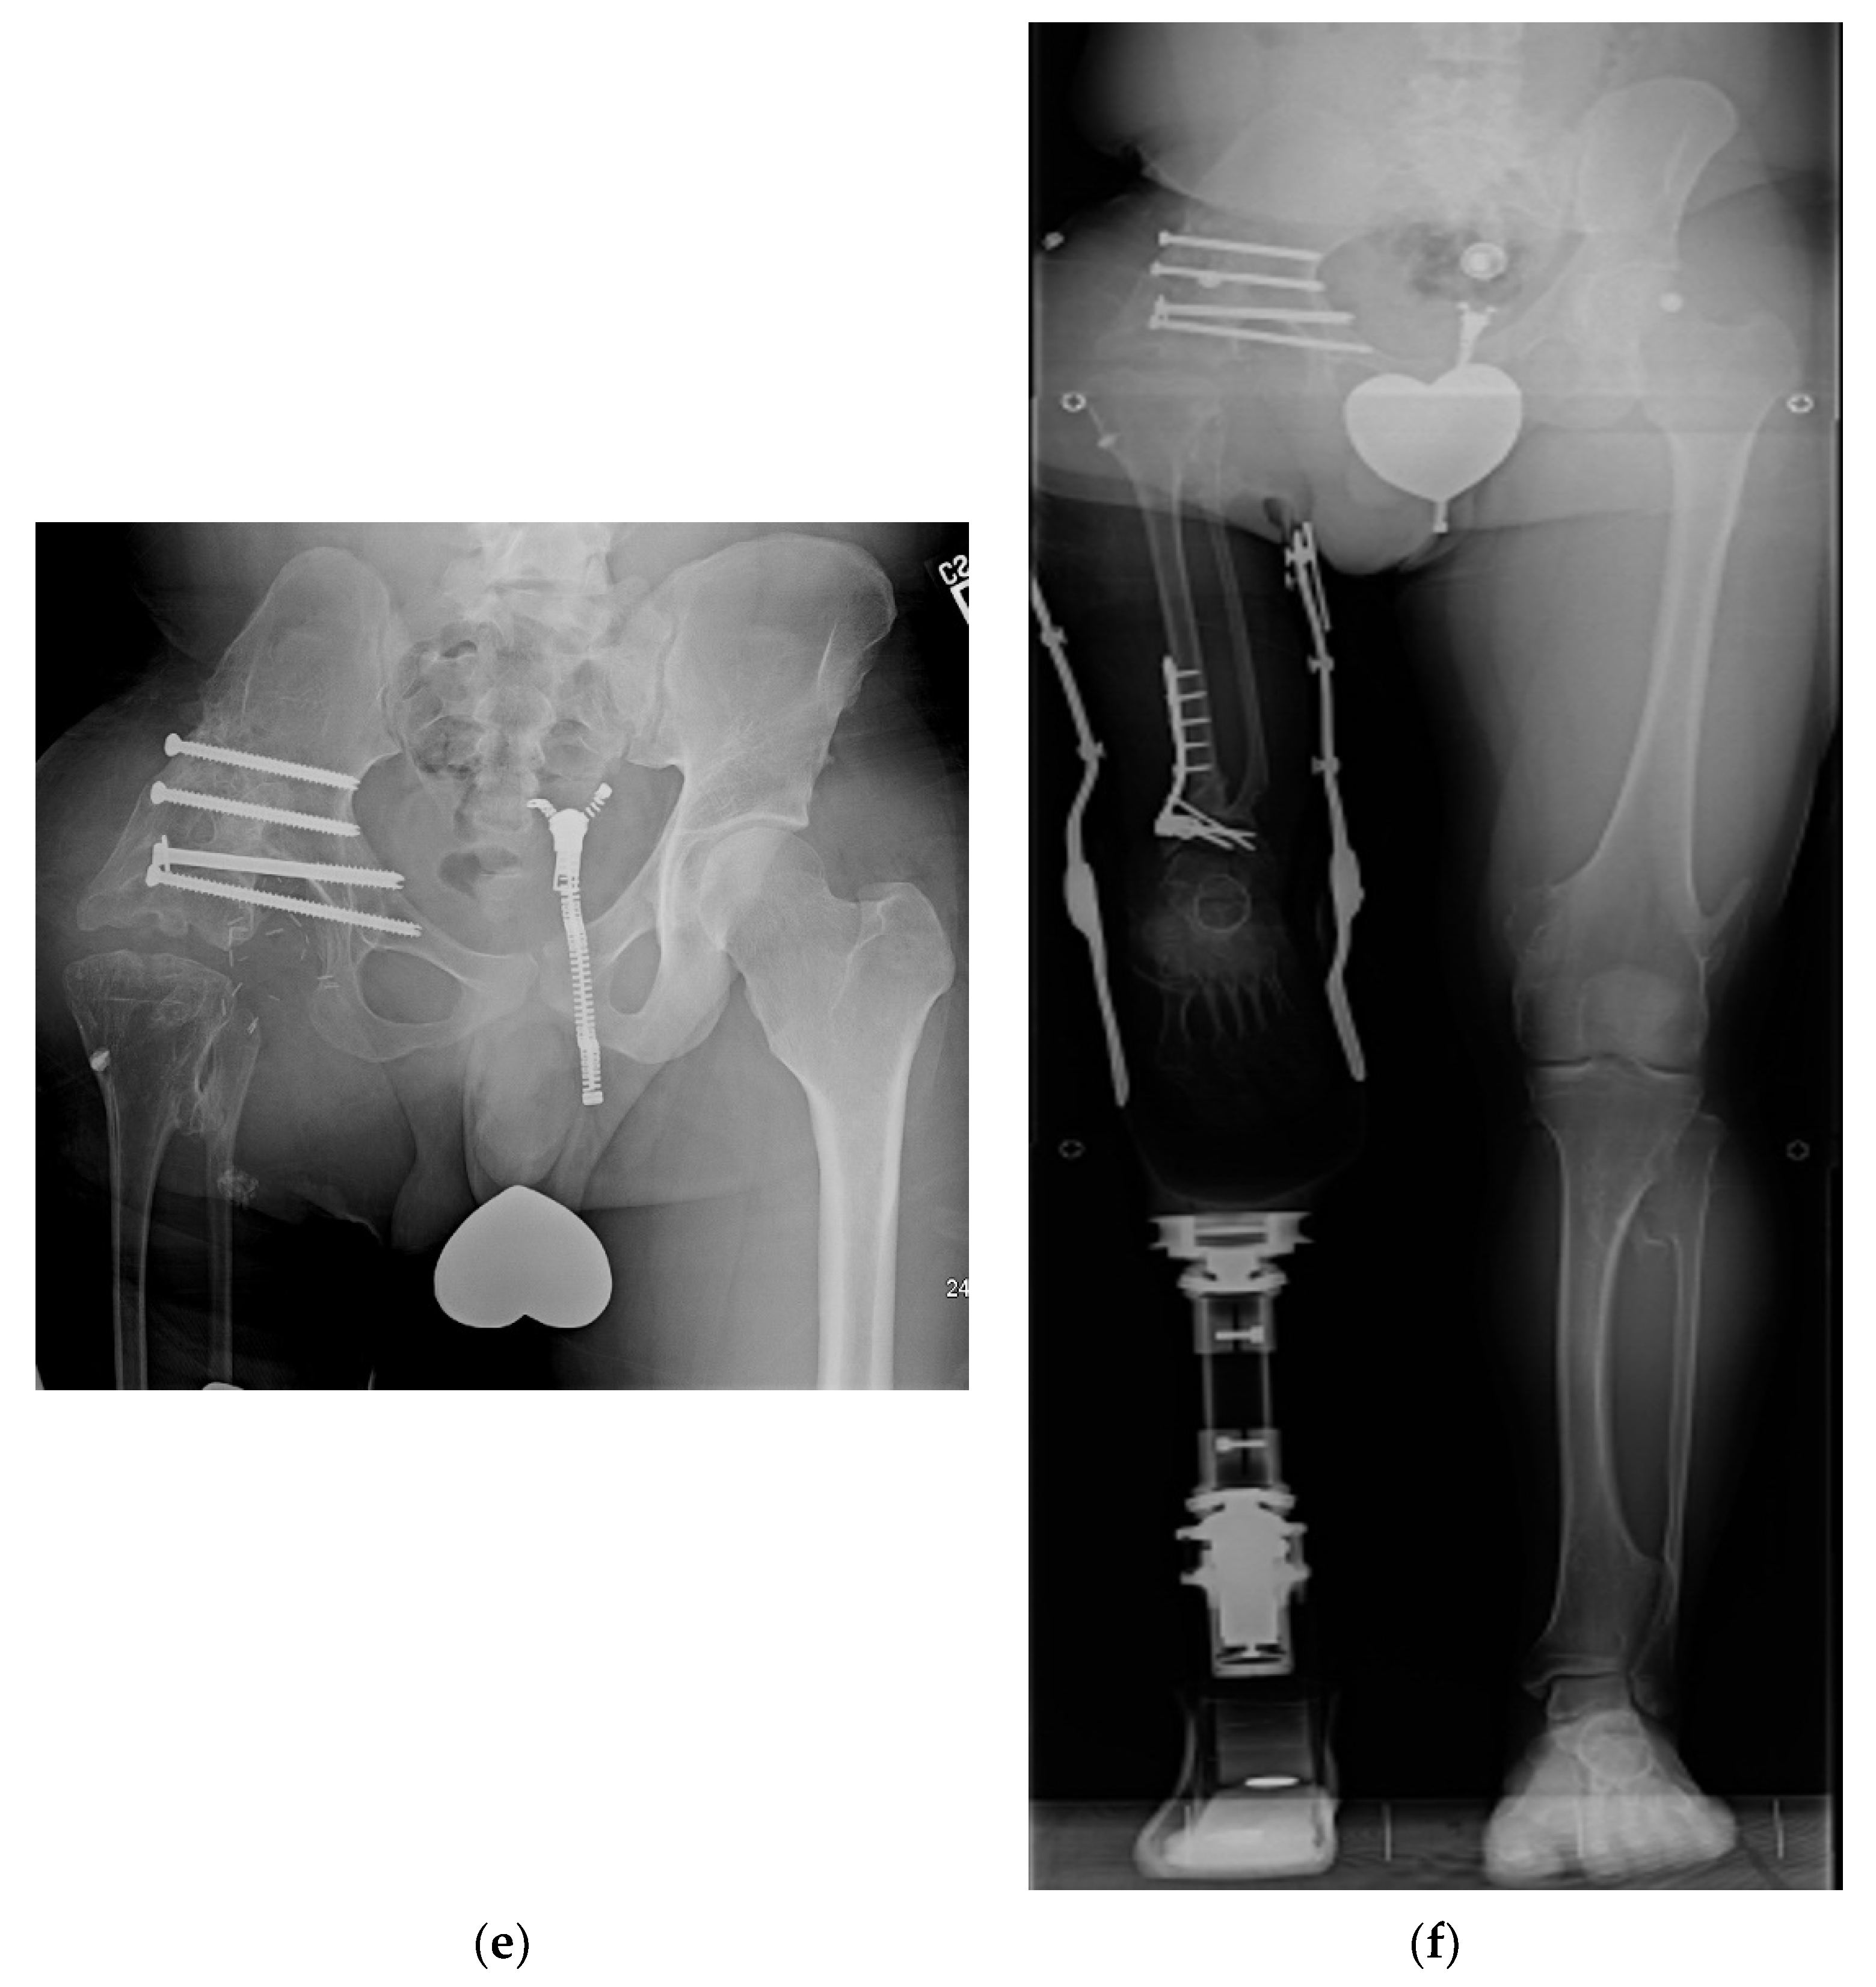

Figure 2.

(a) Illustration of CFD Paley type 3 (a or b), (b) Illustration after Brown rotationplasty for Paley type 3 (a or b), (c) AP pelvis x-ray of 14-year-old boy with Paley type 3b CFD, (d) Preop standing erect leg x-ray of same boy, showing that the ankle is at the level of the opposite knee (incidentally this patient also has multiple osteochondromas), (e) AP pelvis radiograph in same boy, 7 years after healed Brown rotationplasty, (f) Sanding radiograph with prosthetic 7 years after Brown rotationplasty with supramalleolar osteotomy for ankle realignment. Clinically he has excellent gait and function.